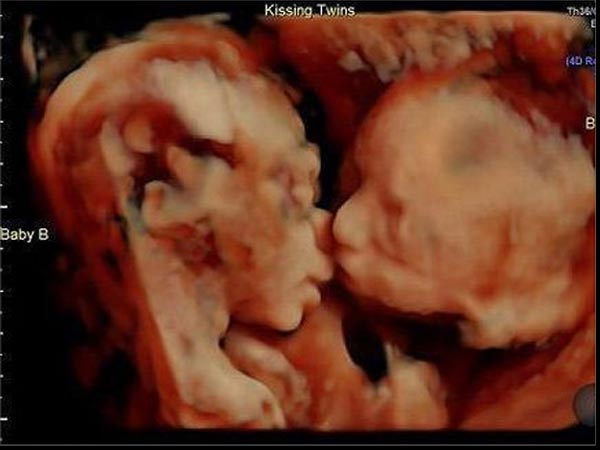

All Thanks To The Technology!

All thanks to the technology, they were able to capture this in their camera. Check out the beautiful picture!

The Couple Cannot Wait Further To Have These Adorable Babies!

Since the ultrasound scan was done, the couple Randy and Carissa are enjoying their parenthood to the maximum. The news of the twins kissing has gone viral that now everyone's waiting for the little ones to come into our world!